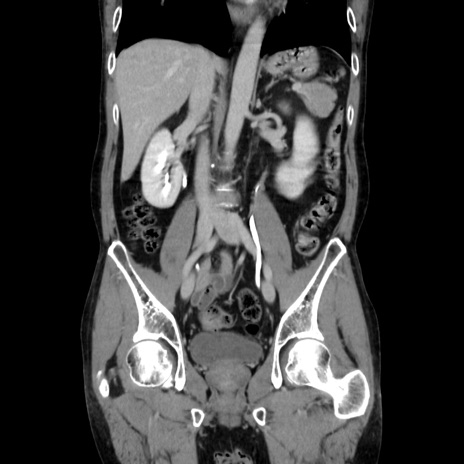

症例37(冠状断像)

【症例】40歳代 男性

【主訴】腹痛

【現病歴】4時間ほど前に電車に乗車中に臍部上より腹痛出現。徐々に増悪し起立困難となり、救急外来受診。生ものは数日食べていない。今朝お雑煮を食べた。

【身体所見】BT 36.8℃、BP 117/84mmHg、HR 91/min、SpO2 97%、苦悶様、腹部:臍上部広範囲圧痛あり、反跳痛±

【データ】WBC 8100、CRP 0.03